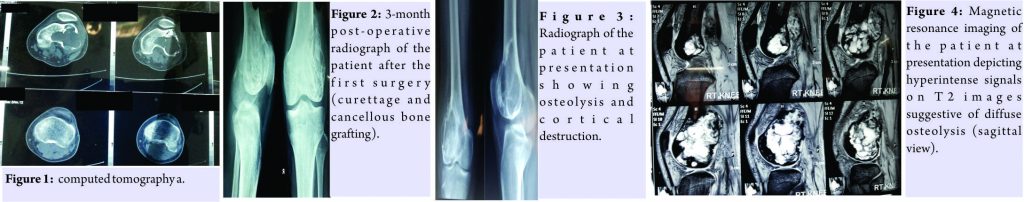

A 25-year-old male presented to us with complaints of painful swelling of his right knee joint with inability to bear weight. He had undergone surgery (done elsewhere) for GCT of lateral condyle of femur 22 months ago in the form of curettage and bone grafting from iliac crest (Fig. 1: Pre-operative and Fig. 2: 3-month post-operative radiograph).

The patient did not relieve his pain in knee joint (which he had before surgery) throughout the course of the treatment. He consulted the primary surgeon for the same and advised active range of motion exercises. The pain kept on increasing, especially in last 6 months, and on examination, he had tenderness over lateral and posterior aspect of knee joint with diffuse swelling and limited range of motion (10–40°) when presented to us. Investigation in the form of radiograph (Fig. 3) depicted diffuse osteolysis and cortical destruction in lateral femoral condyle. Magnetic resonance imagingMRI of the lesion illustrated the heterogeneous decreased signals on T1 sequences and areas of hyperintensities on T2 sequences with overall picture suggestive of recurrence (Fig. 4 and 5).